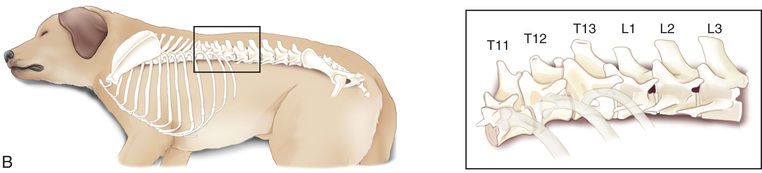

However, in spite of the limitations, proper survey vertebral radiographs are a valuable tool for those patients who have suffered spinal injuries and present with paresis or paralysis, either partial or complete. In addition, survey radiographs can demonstrate many of the signs consistent with intervertebral disk protrusion. Common intervertebral disk protrusion sites are T12 to T13, T13 to L1, C2 to C3, and C3 to C4.1

High-quality images are needed to see subtle changes in bone opacity, shape, and angulation of the vertebrae or vertebral column1,2 (Table 20.1). The common views of this portion of the axial skeleton are the lateral (L) and ventrodorsal (VD) views of the cervical, thoracic, thoracolumbar, lumbar, lumbosacral, sacral, and caudal vertebrae. Depending on the size of the patient, a full survey study is either four or five images of each orthogonal view.